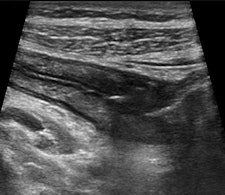

When performing ultrasound of the gastrointestinal tract, there are technical and patient-related challenges. The technical demands include equipment requirements for a broad range of transducer frequencies to allow for scanning of the bowel within the focal range of the transducer so that exceptionally high resolution can be achieved. Although all ultrasound machines have low-frequency probes available, it is the addition of high-frequency probes, both linear and convex, which allows for good bowel assessment, especially in thin patients.

In addition to these technical configurations, the ultrasound equipment must be capable of creating dynamic real-time movie files to show the global perspective of the disease, as well as peristalsis of the bowel. Doppler ultrasound is an essential basic tool as blood flow within the bowel is a possible sign of inflammation.